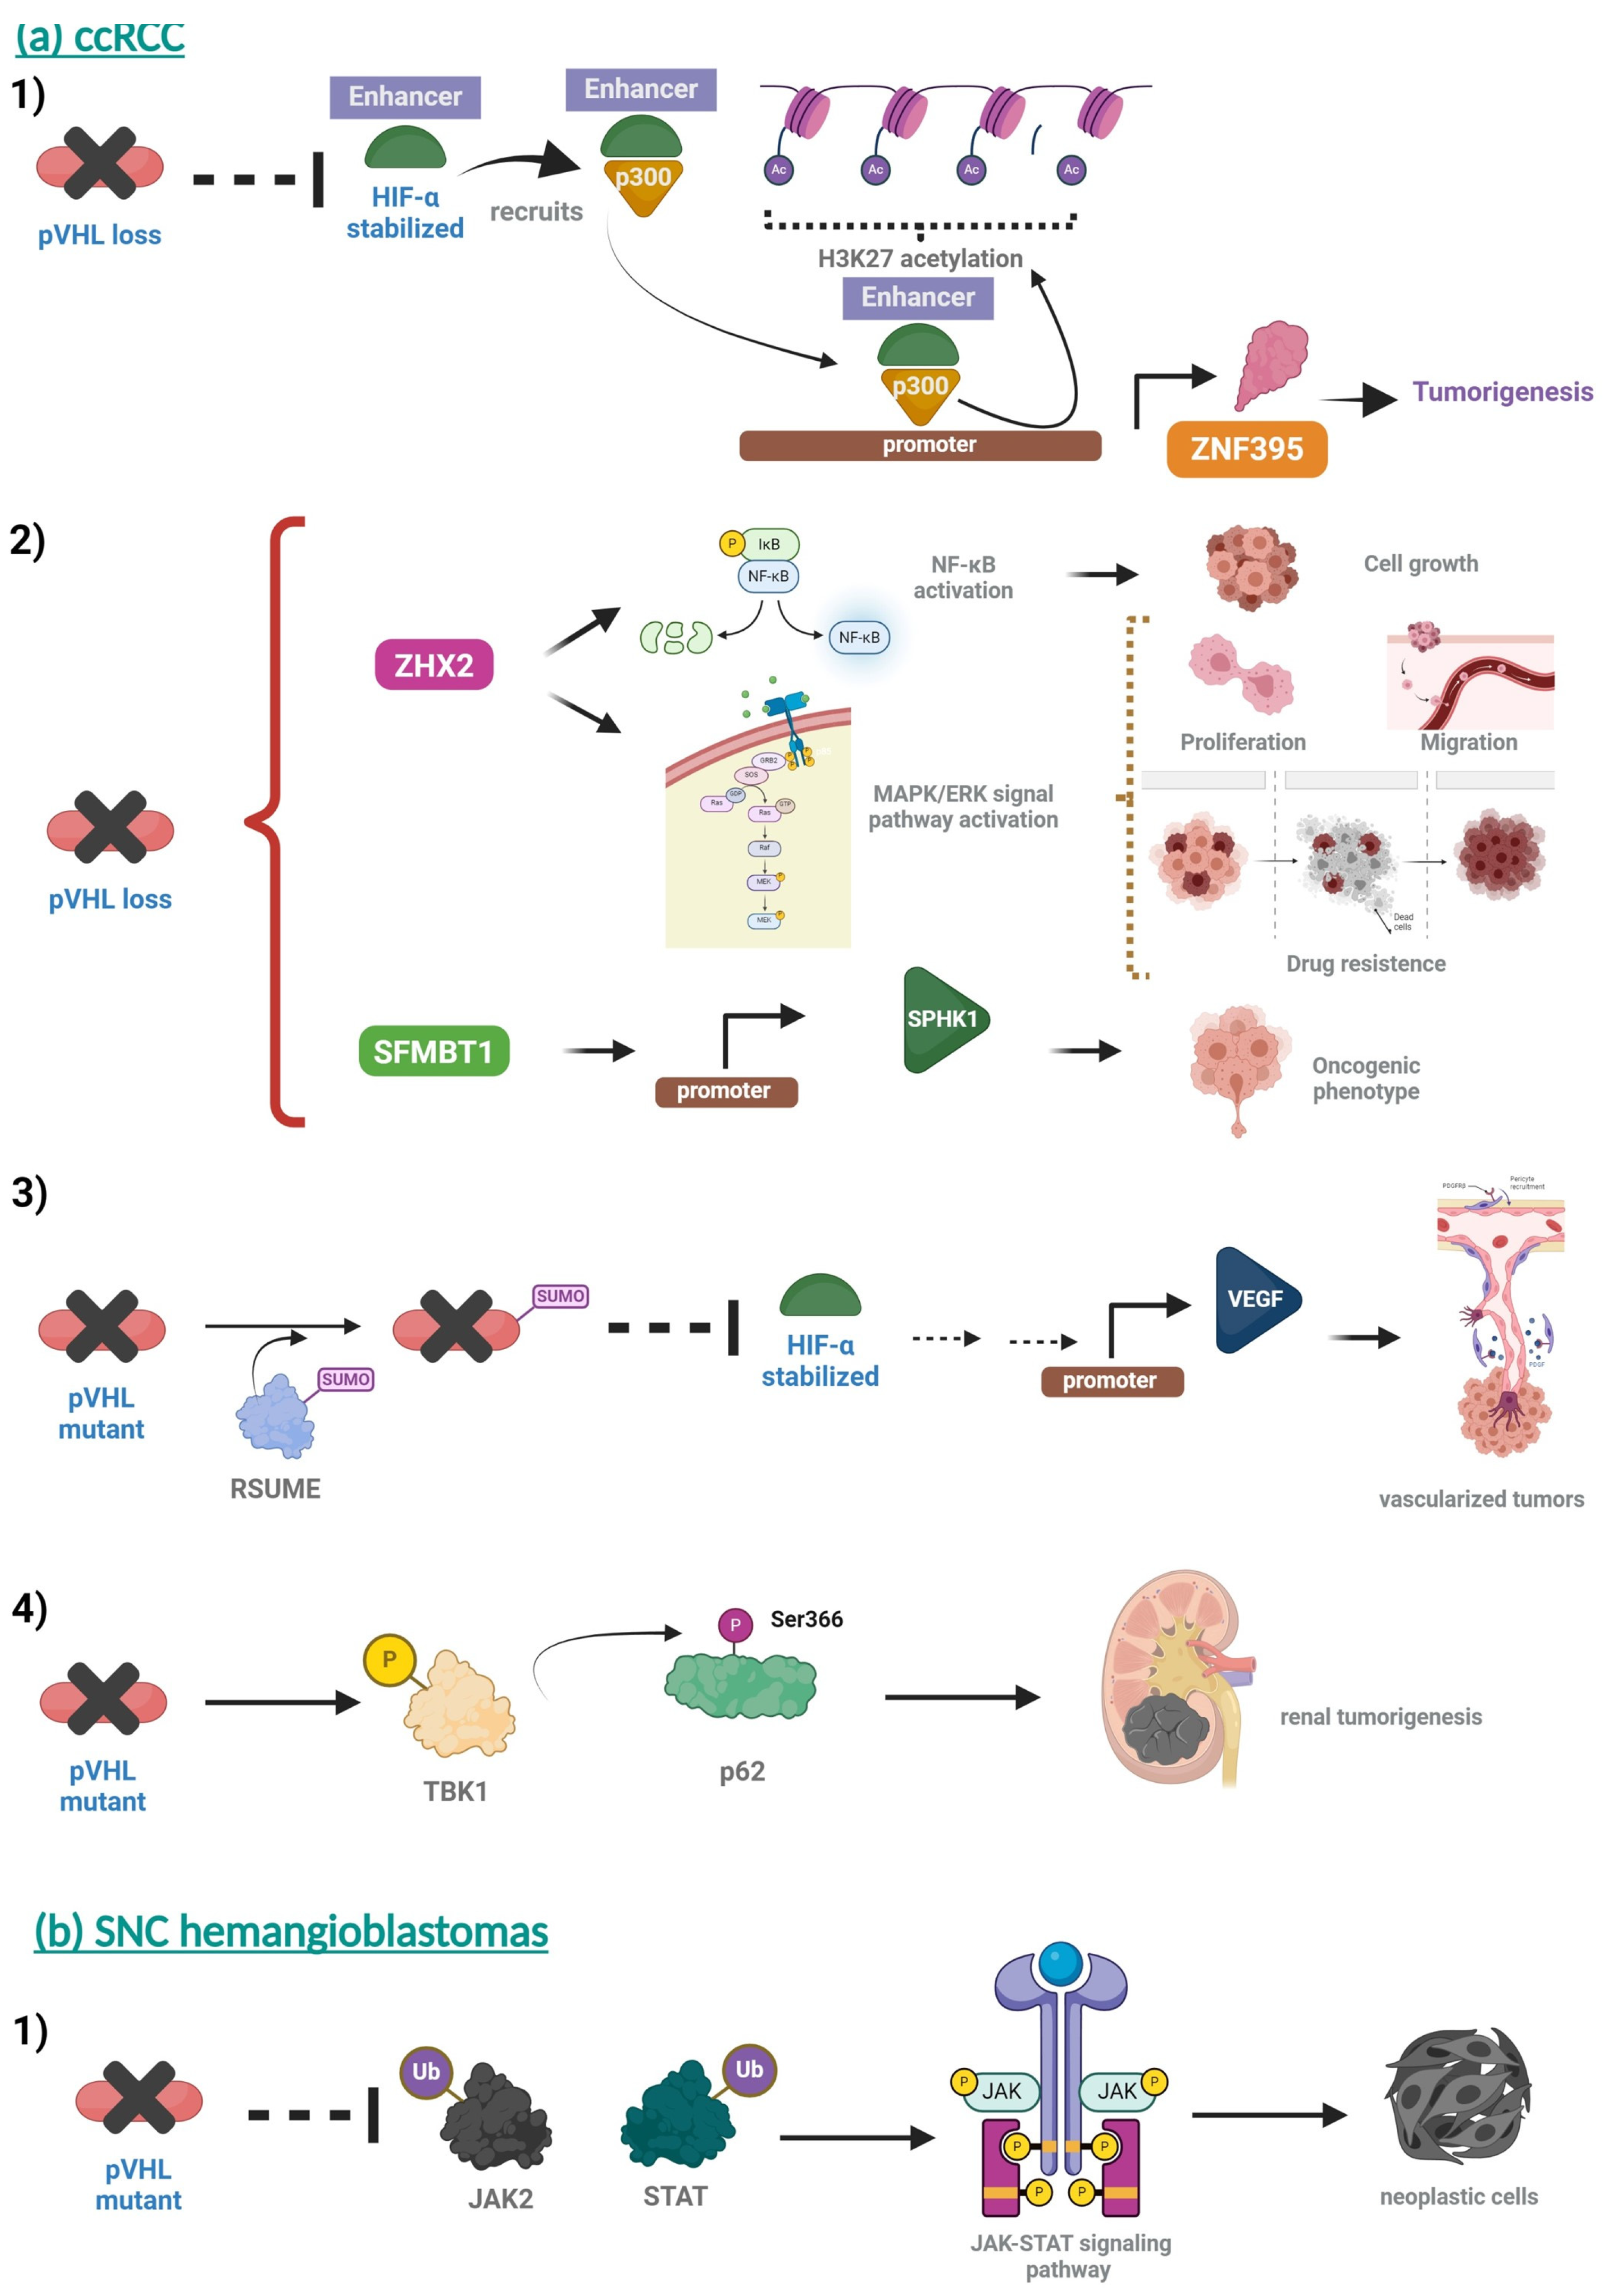

5. Molecular Basis of VHL Disease

- Yao, X.; Tan, J.; Lim, K.J.; Koh, J.; Ooi, W.F.; Li, Z.; Huang, D.; Xing, M.; Chan, Y.S.; Qu, J.Z.; et al. VHL Deficiency Drives Enhancer Activation of Oncogenes in Clear Cell Renal Cell Carcinoma. Cancer Discov. 2017, 7, 1284–1305. [Google Scholar] [CrossRef] [PubMed]

- Zhang, J.; Wu, T.; Simon, J.; Takada, M.; Saito, R.; Fan, C.; Liu, X.D.; Jonasch, E.; Xie, L.; Chen, X.; et al. VHL substrate transcription factor ZHX2 as an oncogenic driver in clear cell renal cell carcinoma. Science 2018, 361, 290–295. [Google Scholar] [CrossRef] [PubMed]

- Zhu, L.; Ding, R.; Yan, H.; Zhang, J.; Lin, Z. ZHX2 drives cell growth and migration via activating MEK/ERK signal and induces Sunitinib resistance by regulating the autophagy in clear cell Renal Cell Carcinoma. Cell Death Dis. 2020, 11, 337. [Google Scholar] [CrossRef]

- Liu, X.; Simon, J.M.; Xie, H.; Hu, L.; Wang, J.; Zurlo, G.; Fan, C.; Ptacek, T.S.; Herring, L.; Tan, X.; et al. Genome-wide Screening Identifies SFMBT1 as an Oncogenic Driver in Cancer with VHL Loss. Mol. Cell 2020, 77, 1294–1306.e5. [Google Scholar] [CrossRef] [PubMed]

- Chen, Y.; Zhu, L.; Xue, S.; Shi, J.; He, C.; Zhang, Q. Novel VHL substrate targets SFMBT1 and ZHX2 may be important prognostic predictors in patients with ccRCC. Oncol. Lett. 2021, 21, 379. [Google Scholar] [CrossRef] [PubMed]

- Tedesco, L.; Elguero, B.; Pacin, D.G.; Senin, S.; Pollak, C.; Garcia Marchinena, P.A.; Jurado, A.M.; Isola, M.; Labanca, M.J.; Palazzo, M.; et al. von Hippel-Lindau mutants in renal cell carcinoma are regulated by increased expression of RSUME. Cell Death Dis. 2019, 10, 266. [Google Scholar] [CrossRef] [PubMed]

- Hu, L.; Xie, H.; Liu, X.; Potjewyd, F.; James, L.I.; Wilkerson, E.M.; Herring, L.E.; Xie, L.; Chen, X.; Cabrera, J.C.; et al. TBK1 Is a Synthetic Lethal Target in Cancer with VHL Loss. Cancer Discov. 2020, 10, 460–475. [Google Scholar] [CrossRef]

- Kanno, H.; Yoshizumi, T.; Shinonaga, M.; Kubo, A.; Murata, H.; Yao, M. Role of VHL-JAK-STAT signaling pathway in central nervous system hemangioblastoma associated with von Hippel-Lindau disease. J. Neurooncol. 2020, 148, 29–38. [Google Scholar] [CrossRef]